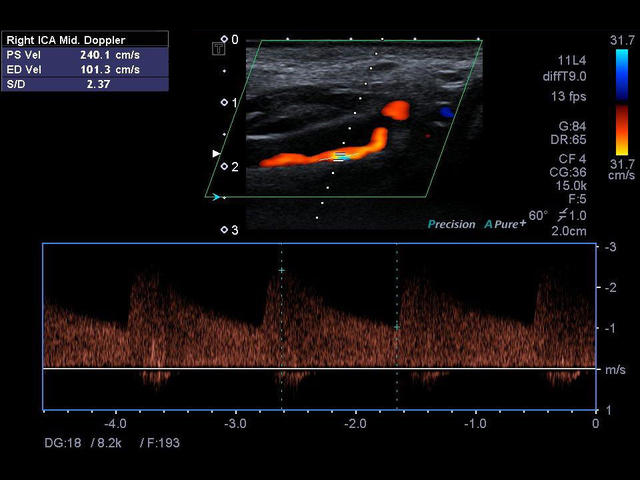

Xario 200 — это продуманная эргономика, впечатляющее качество изображения, отлаженный рабочий процесс и предельно высокая компактность. В Xario 200 цветовая доплеровская визуализация вышла на качественно новый уровень. Полностью интегрированная система управления данными пациентов и изображениями системы Xario обеспечивает удобный просмотр и простое управление исследованиями.

- Автоматическое измерение толщины комплекса интим-медиа (Auto IMT).

- Импульсно-волновой допплер - Pulsed Wave Doppler (PWD).

- Цветной, энергетический допплер - Colour Doppler Imaging/ Color Angio (CDI/CA).

- Модуль высокой частоты повторения импульсов - High pulse rate frequency (HPRF).